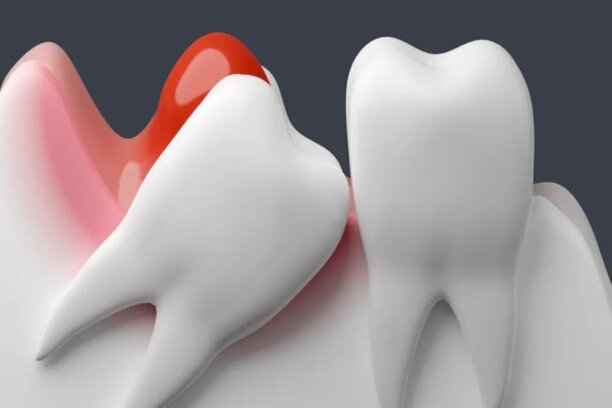

ضرس العقل هو الضرس الثالث والأخير في كل ربع من أرباع الفم، ويُعرف علميًا باسم الضرس الطاحن الثالث. يتميز بموقعه الخلفي العميق، ما يجعله أكثر عرضة للمشكلات مقارنة ببقية الأسنان. غالبًا ما يكون بزوغه غير مكتمل أو منحرفًا بسبب ضيق المساحة، الأمر الذي يؤدي إلى سلسلة من المشكلات المتتابعة. وهنا تبدأ اعراض ضرس العقل في الظهور تدريجيًا، كتنبيه بيولوجي بأن هذا الضرس لا يسلك المسار الطبيعي للنمو. ومع استمرار الضغط والاحتكاك، تتفاقم اعراض ضرس العقل وتتحول من مجرد انزعاج إلى ألم حاد قد يؤثر على جودة الحياة اليومية.

يختلف شكل ضرس العقل من شخص لآخر، إلا أنه غالبًا ما يتميز بحجم أكبر وجذور أكثر تعقيدًا مقارنة ببقية الأضراس. قد يكون مكتمل التكوين أو مشوهًا جزئيًا، وقد يظهر بشكل عمودي أو مائل أو حتى أفقي. هذه الاختلافات الشكلية تلعب دورًا مباشرًا في حدة اعراض ضرس العقل. ومن أبرز السمات الشكلية الشائعة:

• ميلان واضح نحو الضرس المجاور أو باتجاه عظم الفك.

• بزوغ جزئي يترك جزءًا من الضرس مغطى باللثة.